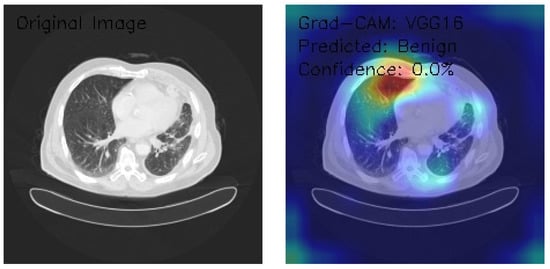

VGG16 Model Analysis of Lung CT Images with Grad-CAM Visualization

The results section of this analysis provides a detailed examination of three axial chest CT images analyzed through the VGG16 architecture, a widely recognized convolutional neural network model. We employed Grad-CAM, an advanced visualization technique, to gain insights into the model’s decision-making processes and focus areas. This method highlights the regions of the input images the model considers most significant when making predictions, offering a comprehensive view of its attention patterns. By integrating Grad-CAM with the VGG16 framework, this analysis illustrates the model’s effectiveness in interpreting medical imaging data and provides a transparent mechanism to evaluate its decision rationale. The findings presented aim to shed light on the nuanced interactions between the neural network and the image features, contributing to the broader understanding of AI-assisted diagnostic methodologies.

Figure 16 shows the CT image demonstrating interstitial patterns with branching structures, and the Grad-CAM visualizations indicate bilateral peripheral activation, with strong emphasis along the lateral chest wall interfaces. The model classifies the image as Benign with a confidence score of 0.0%, reflecting significant uncertainty in its decision-making process despite the clear focus on relevant anatomical regions. The bilateral peripheral activation pattern suggests that the model effectively identifies features of interest, but the low confidence highlights a disconnect in translating these observations into reliable classifications. Enhancing the model’s calibration and optimizing its classification layers are crucial to improving its clinical utility.

Figure 16.

The VGG16 model, applied to three chest CT images with Grad-CAM visualizations, demonstrates strong capabilities in localizing anatomical features but struggles with reliable classification due to uniformly low confidence scores. Image A, showing scattered nodular opacities, reveals intense bilateral upper lung activation with a predominant right-sided focus, yet is classified as Normal with 0.0% confidence. Image B highlights peripheral lung field activation and lateral chest wall emphasis in the presence of interstitial patterns, classified as Benign with 0.0% confidence. Image C, featuring clear lung fields, displays focal activation in the right upper lung and hilar regions, but is similarly classified as Benign with 0.0% confidence. While the model excels in highlighting regions of interest with precise and consistent attention patterns, its limited confidence and conservative classification behavior highlight the need for calibration and optimization. These findings suggest potential utility in feature detection and initial screenings, provided enhancements to confidence scoring and classification thresholds are implemented.